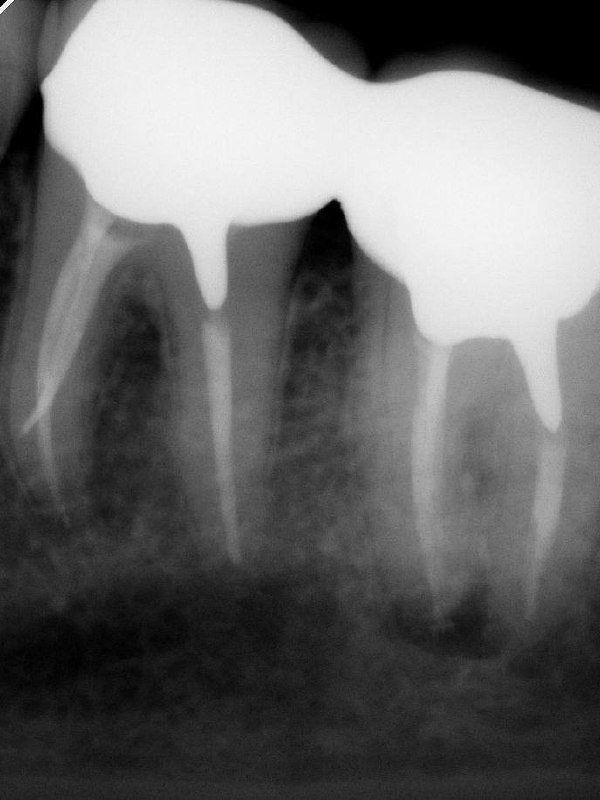

Кейс: крестальная перфорация на 4 мм от альвеолярного гребня с разрежением кости и пародонтальным карманом — в данном случае показано удаление.